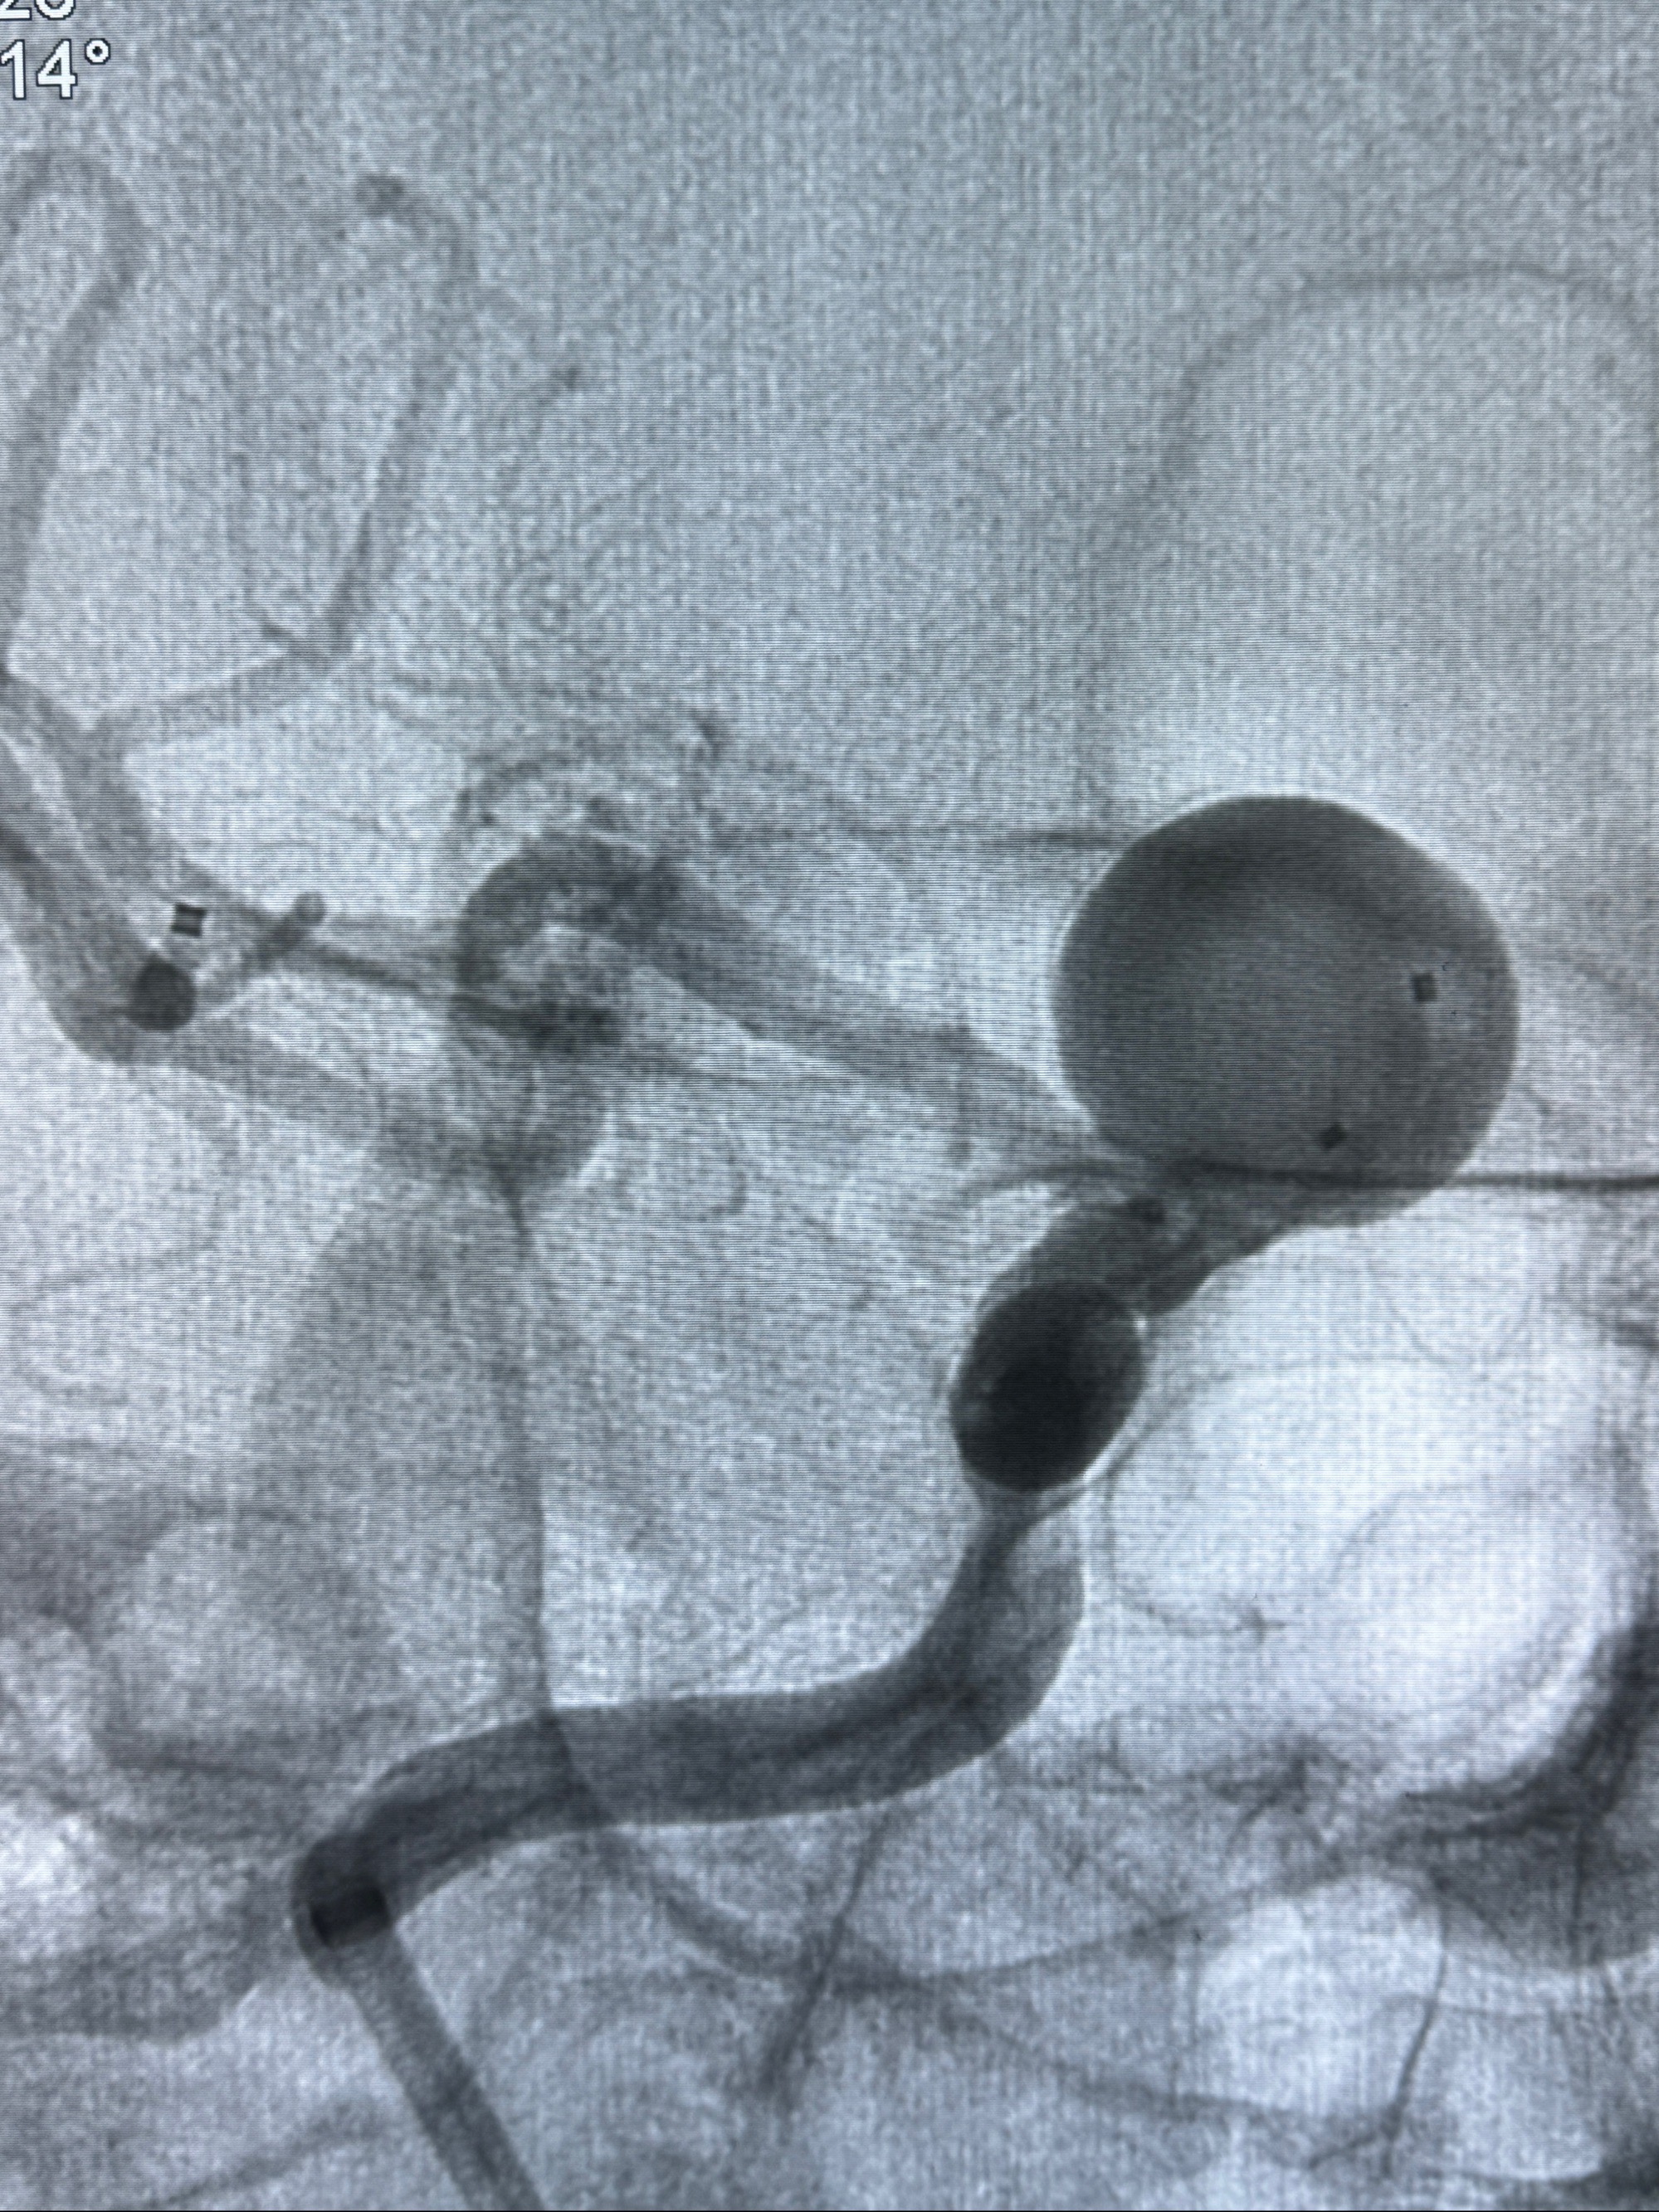

2023-12-08 复旦大学附属华山医院 全脑血管造影:右侧颈内动脉C6段动脉瘤,瘤颈6.68mm,动脉瘤大小13.28*12.34mm

2023-12-08外院DSA:右侧颈眼动脉瘤,约13*12mm大小,压颈试验显示左右向及后向前代偿可

测量动脉瘤的大小:16*13.8*7.6mm大小,较原先变大,考虑双抗后瘤内血栓溶解可能